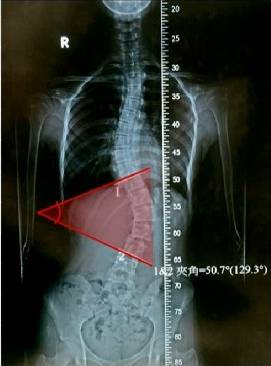

Minggu (8/7) gadis asal Kaohsiung, Taiwan ini mengalami perubahan sekitar 50 derajat pembengkokan tulang belakang dan mengalami kesakitan punggung yang cukup hebat, dan ibu dari gadis ini membawanya ke bagian ortopedi untuk diperiksa lebih lanjut.

Setelah diperiksa, diketahui bahwa pembengkokan tulang belakang yang cukup banyak ini berawal dari kebiasaan si gadis yang sering bermain hp dengan badan menyamping saat tidur. Rutinitas ini ternyata berpengaruh pada posisi tulang belakangnya yang kemudian berubah menjadi sakit punggung yang berkepanjangan.

Dokter juga mengatakan, otot dari punggung gadis ini juga sudah tidak kuat menahan bobot tubuhnya yang sering menyamping dan tidak diimbangi dengan olahraga. Untuk mengatasi pembengkokan tulang tersebut, akhirnya gadis ini untuk sementara harus menjalani terapi agar tulangnya kembali seperti sedia kala.